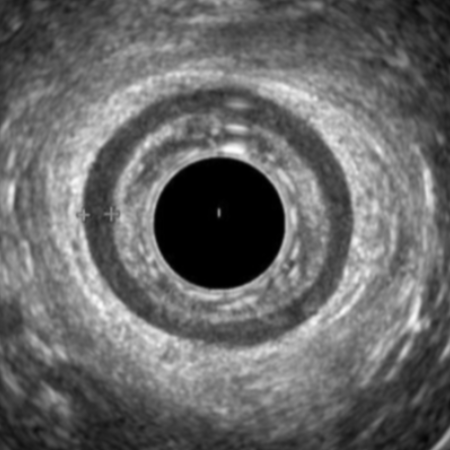

Endoanal Ultrasound

Understand the technique and interpretation of this essential Pelvic Floor modality.